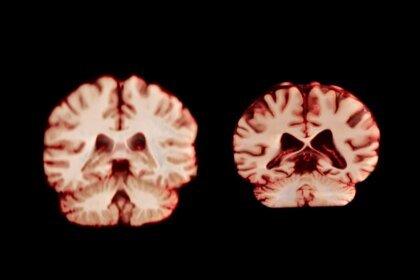

Males’s Brains Shrink Sooner than Ladies’s. What That Means for Alzheimer’s